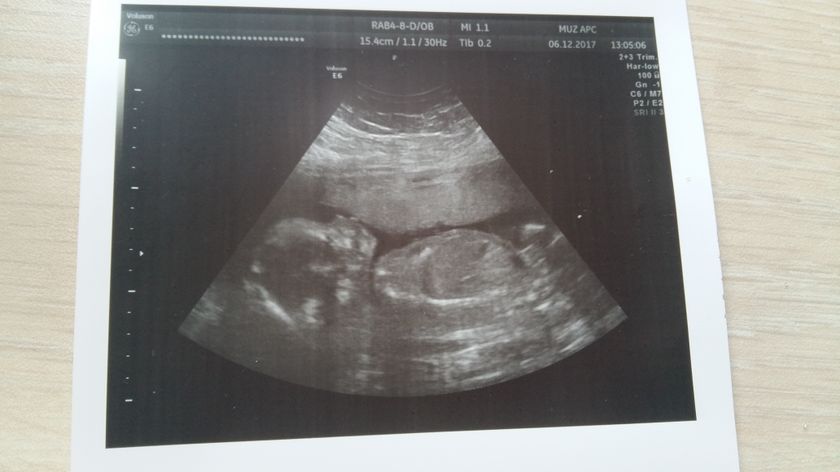

Все хорошо у нас ???? мальчик!!! Мужик.… а ааа я мама двух сыновей ??. Почему то всегда была уверена, что у меня одни девочки могут быть ??. Не умею я мальчиков воспитывать… балую и залюбливаю очень ??. Но Богу виднее ?? буду учиться… Главное что все хорошо!!! Вес 350 грамм, рост 27см ??. Еще не родила а уже не могу налюбоваться им на фотке ??? ну очень сумасшедшая мамаша ???. Мой сладкий и бесконечно любимый ??????????? малыш. Мое счастье ??????? мама уже готова тебя нацеловывать ???????

Красотуля))) как будто губки тянет целоваться)))

Такой спокойный кроха) мой вообще ручки не опускал

Да нет так поймали. Во время УЗИ очень активничал ?